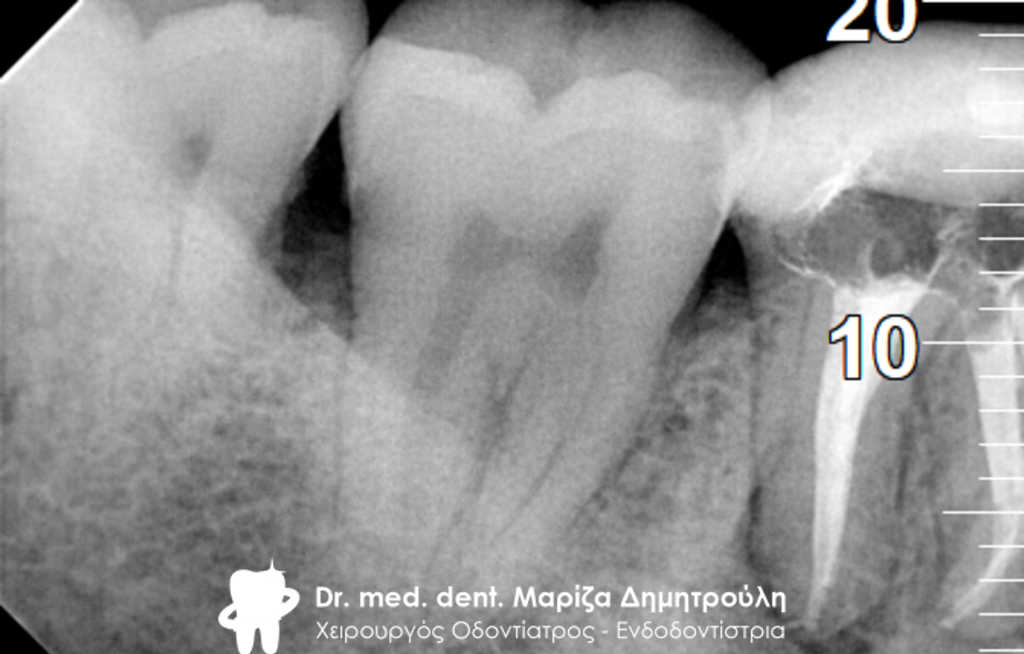

Ο ασθενής πονούσε πολύ στον άνω γομφίο, που είχε απονευρωθεί πριν από χρόνια. Αποφασίστηκε η επανάληψη απονεύρωσης του δοντιού, κατά την οποία διαπιστώθηκε οτι υπήρχε και τέταρτος ριζικός σωλήνας που δεν είχε βρεθεί και επεξεργαστεί κατά την πρώτη προσπάθεια απονεύρωσης. Πλέον το δόντι είναι ασυμπτωματικό.

Παλιά απονεύρωση του δύο άνω γομφίου

Νέα απονεύρωση στον άνω γομφίο